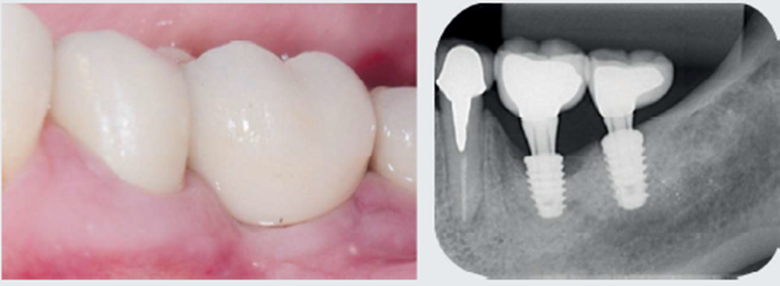

Paciente do sexo feminino com 51 anos de idade, não tabagista, sem histórico de doença sistêmica ou uso contínuo de medicamentos, foi diagnosticada em 2018 com peri-implantite após 27 meses de implantação e 23 meses de reabilitação protética. Quatro meses antes da instalação dos implantes, ela foi submetida a enxerto gengival livre para aumento de tecido queratinizado na região dos dentes 36 e 37. Após dois anos de tratamento, relatou queixa de sensibilidade, inicialmente discreta, mas que evoluiu durante algumas semanas para uma dor pulsátil e contínua que era controlada somente com o uso de analgésicos. No exame clínico, foi constatada a presença de eritema discreto e profundidade de sondagem de 7 mm, associado a sangramento e secreção no sulco. Foi solicitada uma radiografia periapical que evidenciou a perda óssea tipo crateriforme, comprometendo aproximadamente metade do comprimento do implante (Figura 1). Após orientações e acordo das possibilidades terapêuticas, além dos riscos e benefícios envolvidos, a paciente foi submetida a tratamento cirúrgico para descontaminação e regeneração do defeito associado.

Após mais de 18 meses de proservação, observou-se um excelente resultado no controle da infecção peri-implantar e na regeneração do defeito ósseo (Figura 7). Com quatro anos de controle pós-tratamento, na avaliação clínica e nas imagens da proservação radiográfica e tomográfica, foi possível observar aspectos de estabilidade no tecido ósseo regenerado e compatíveis com a saúde dos tecidos peri-implantares (Figuras 8 e 9).